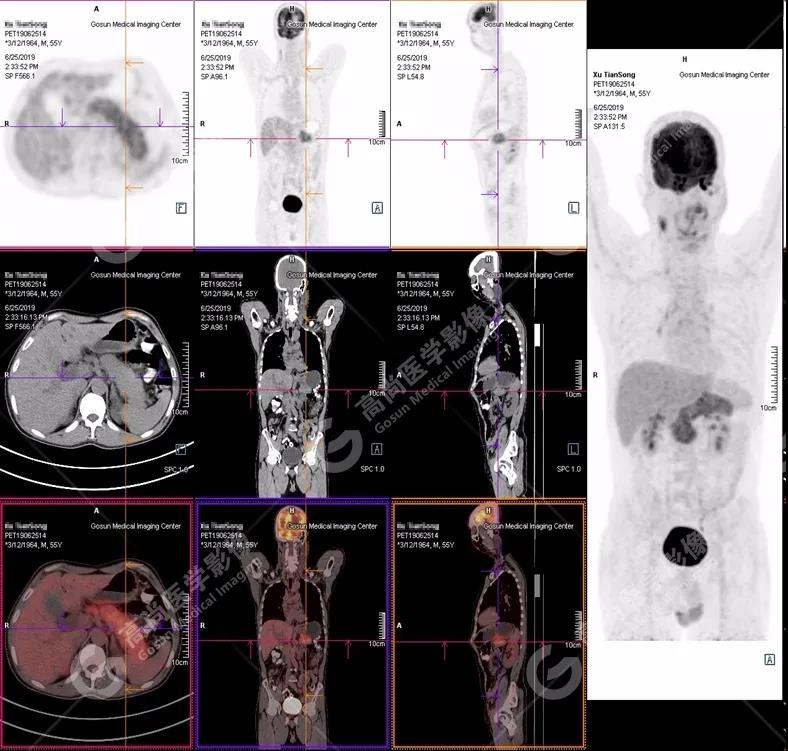

PET/CT 全身圖

胰腺腫脹、密度均勻,代謝彌漫性不均勻增高,SUV最大值5.2 平均值4.0

(1)胰腺輕度腫脹,胰腺體尾部胰管狹窄,未見(jiàn)明顯占位性病變,代謝彌漫性增高。

(2)胰周(胰胃間隙)稍大淋巴結(jié),代謝增高。

(3)全身其它部位未見(jiàn)明顯高代謝惡性腫瘤征象。